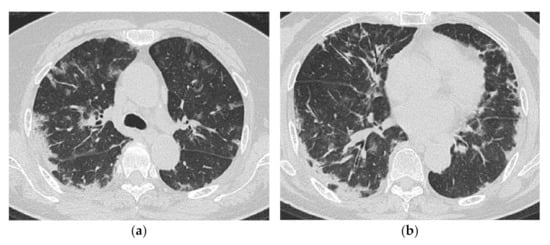

2.1. Subacute to Chronic Type

2.2. Acute Type

| Chronic to Subacute | Acute |

|---|---|

| Subacute course of disease > chronic | Acute or subacute onset, often with a rapid progressive course |

| Predominantly in the lower lobes of both lungs | Diffuse, or diffuse with a predominance of the lower lung zone |

| Peribronchovascular bundle distribution | Peribronchovascular distribution in the lower lobes, with parallel extension to the pleura |

| Reticular shadows and consolidation are common | GGO and consolidation |

| Reduced volume of the lower lobes | Basal volume loss |

| Traction bronchiectasis |